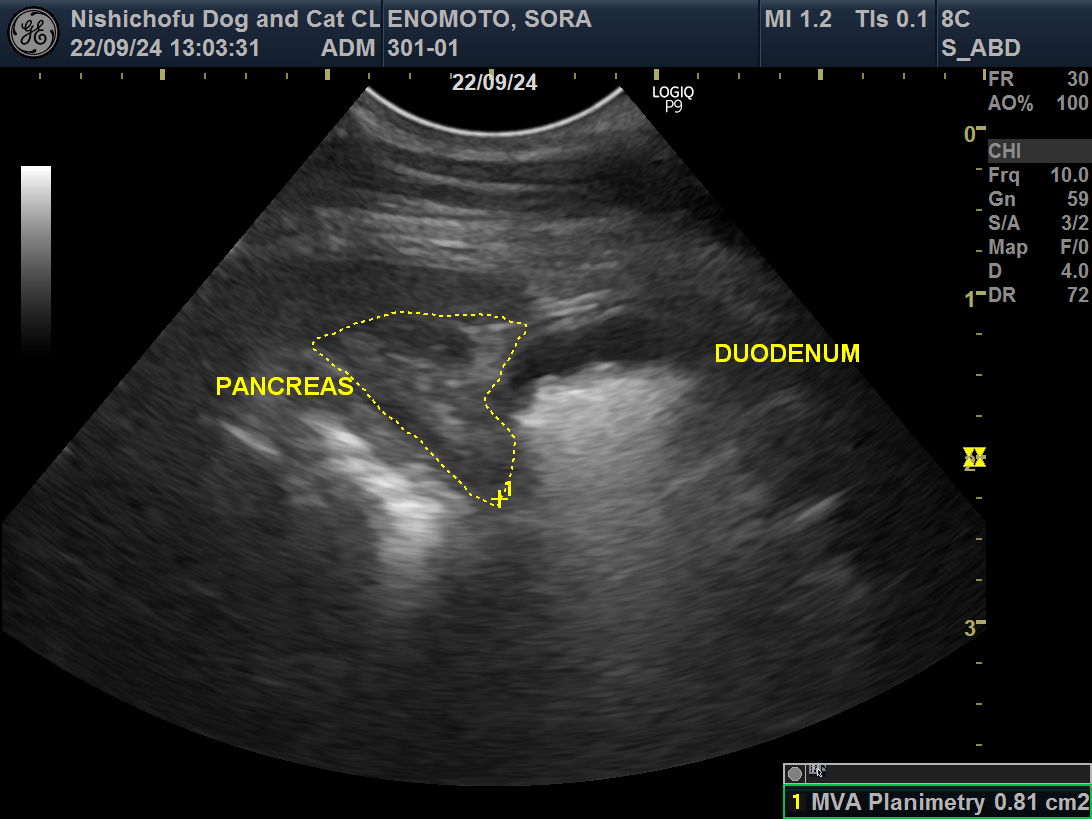

炎症を起こしている膵臓(PANCREAS)。